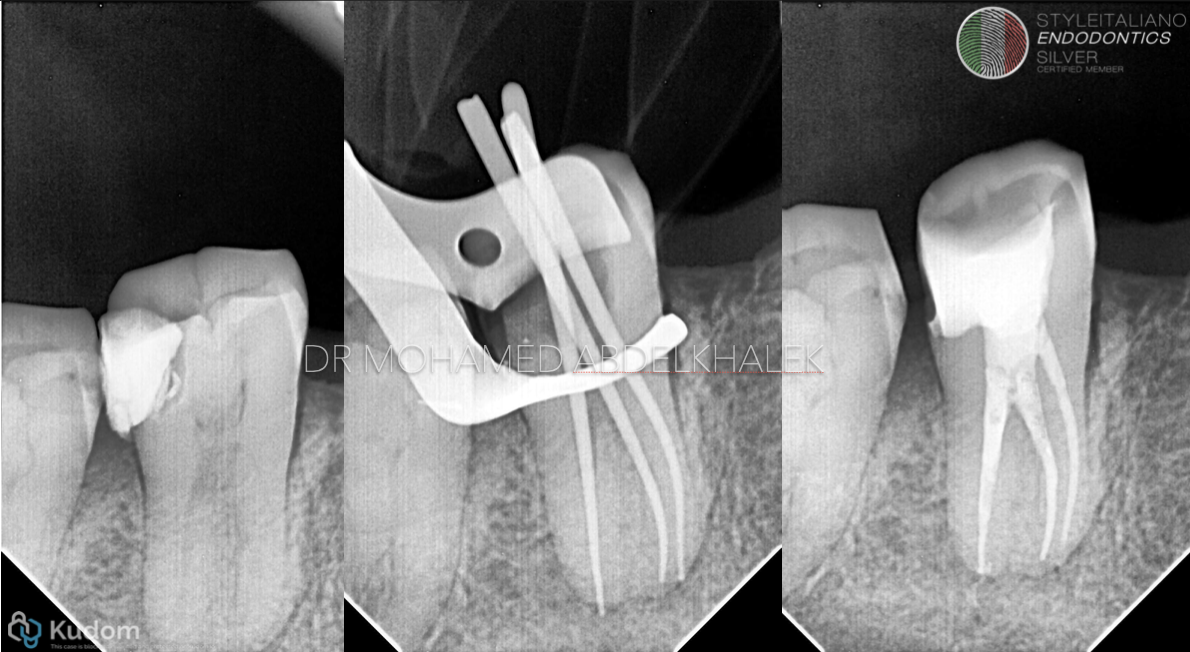

Fig. 1

The C-shaped canal configuration is characterized by a continuous or semi-continuous fin or web connecting individual canals, forming a "C"-shaped cross-section.

This anatomical variation results from the failure of Hertwig's epithelial root sheath to fuse on either the buccal or lingual surface during root development.